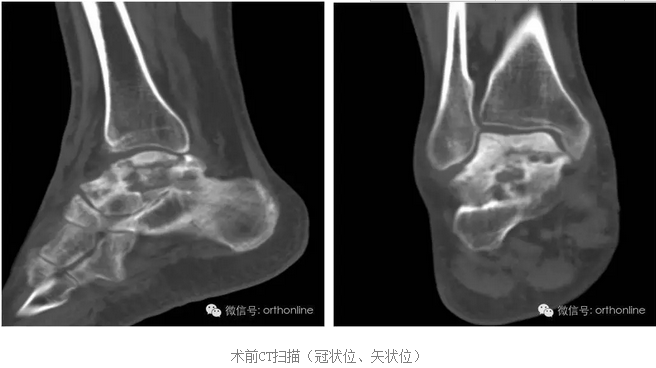

创伤引起的距骨塌陷性坏死一直是医学界面临的难题,治疗手段非常有限,目前只能采用以牺牲踝关节生物学功能的胫-距-跟植骨融合来缓解病人的痛苦,严重影响患者生活质量。

针对上述问题,由第三军医大学西南医院唐康来教授牵头,中国科学院重庆绿色智能技术研究院、物质结构研究所、金属研究所、化学研究所、理化技术研究所等十个单位协作攻关,分别从3D打印设备与专用材料、个体性产品开发与临床应用方面进行研究,研制了世界上首个3D打印的具有生物学功能的个性化距骨假体,于2016年7月4日在重庆第三军医大学西南医院成功应用于创伤引起的距骨塌陷性坏死病例。

假体制作完全忠实于患者个体的解剖结构,术前将健侧的骨性解剖数据进行镜像处理,获得个性化假体数据源;3D打印完成后再将假体扫描,与数据源进行耦合对照检测;假体植入后扫描患肢,检测与数据源耦合性能;

塌陷性距骨坏死一直是踝关节假体置换的绝对禁忌症,该假体打破了常规,为塌陷性距骨坏死提供了非常好的选择。